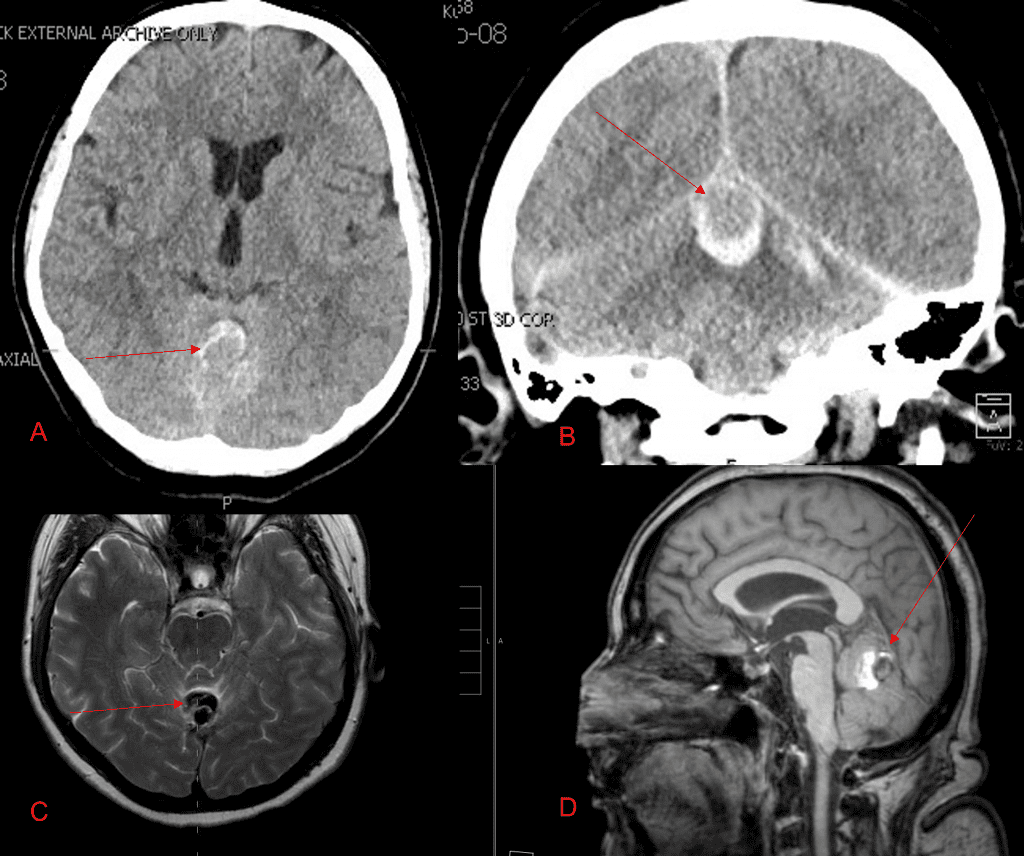

Brain:

Cerebellar Hemangioblastoma

Author: Michael Brisman M.D., F.A.C.S., Read More!

Cerebral Metastases from Non-Small Cell Lung Cancer

Author: Xavier P. J. Gaudin D.O., F.A.C.O.S., Read More!

Grade II Oligodendroglioma

Author: Ramin Rak M.D., F.A.A.N.S., F.C.N.S., Read More!

Pituitary Tumor with Cushing’s Disease